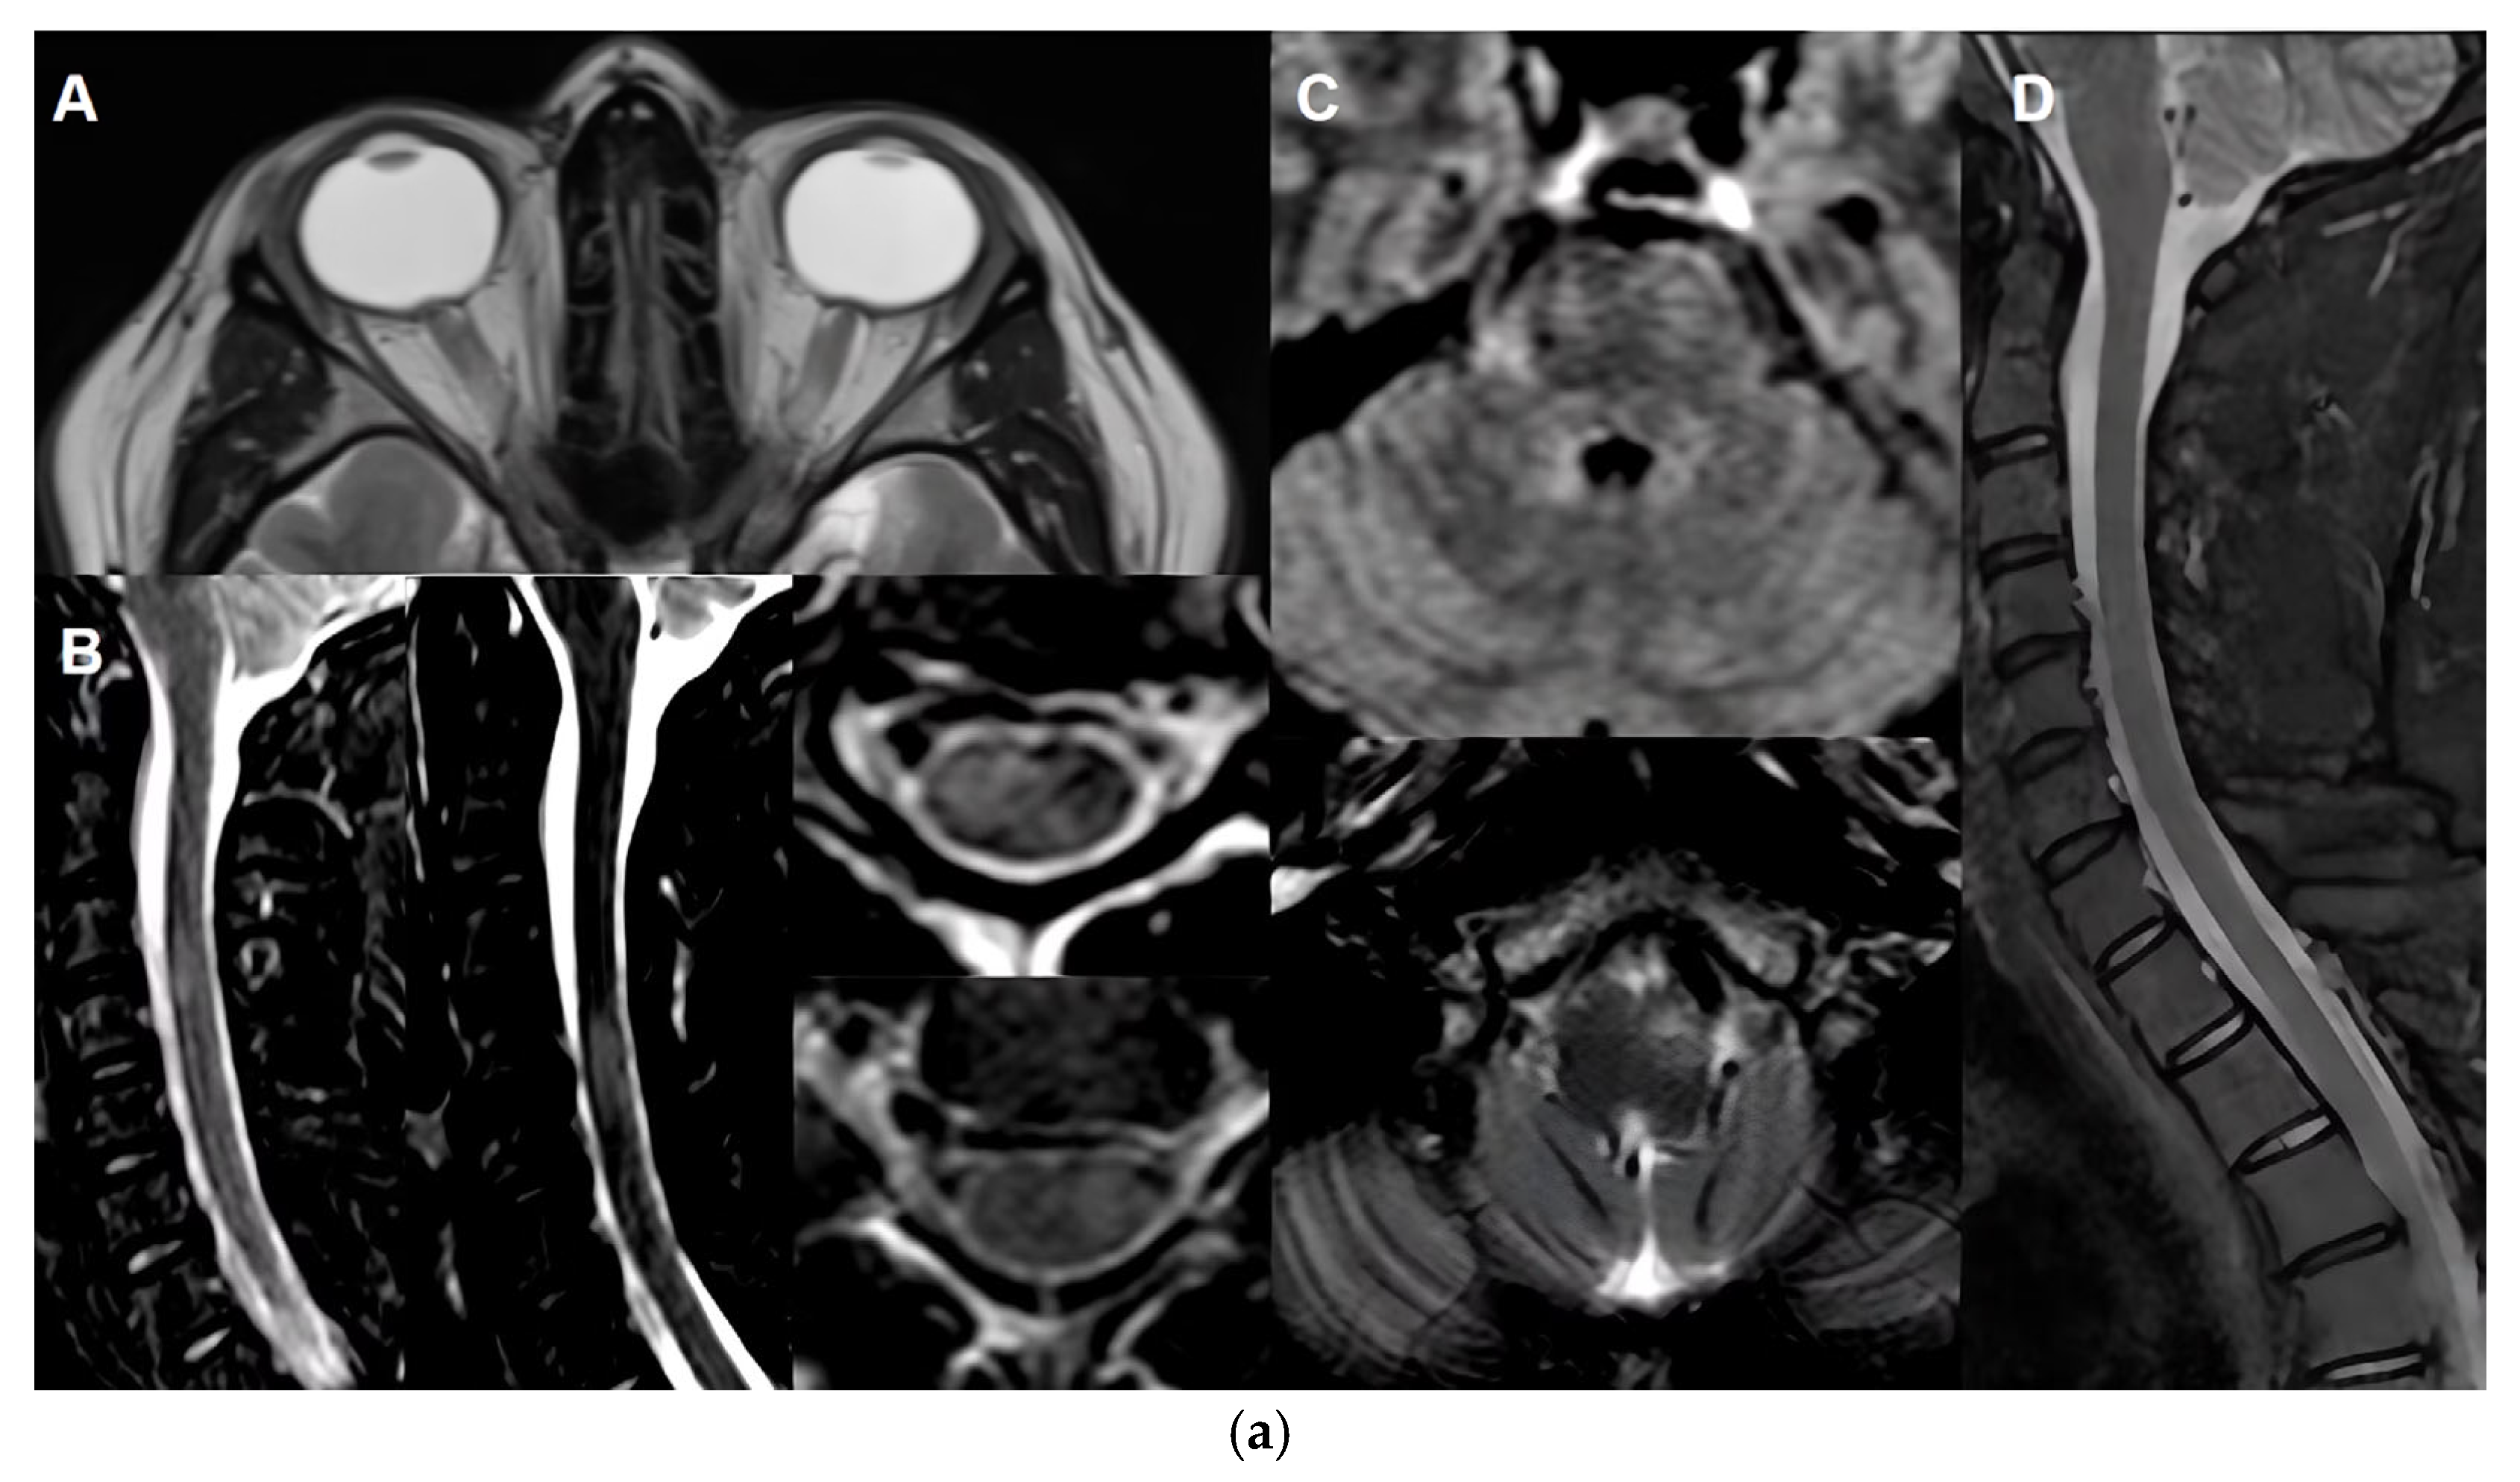

The six core clinical syndromes of MOGAD reflect its diverse neurological involvement. Optic neuritis (ON) is the most common presentation in adults, occurring in 50–60% of cases. It is frequently bilateral and characterised by severe visual loss and optic disc oedema. Despite the severity of initial symptoms, visual recovery in MOGAD-ON is generally more favourable than in AQP4+NMOSD. Transverse myelitis (TM) is another hallmark feature, typically presenting as longitudinally extensive lesions with conus medullaris involvement and a predilection for grey matter. Patients often experience motor, sensory, and autonomic dysfunction. Some patients may present with clear symptoms and neurological signs consistent with transverse myelitis, yet show no evident lesion on MRI. This phenomenon can be explained by imaging performed too early—before lesions become radiologically apparent—or by transient lesions that resolve quickly, leaving only a narrow window for detection. In many cases, MRI findings may normalize after the clinical attack. A small proportion of patients may never show any lesion on MRI, which underscores the importance of clinical judgment. In such scenarios, clinicians must carefully differentiate between a true relapse and a pseudorelapse in patients already diagnosed with MOGAD, or consider MOGAD as a potential diagnosis in patients presenting with evident transverse myelitis but negative MRI findings [18,19]. In pediatric populations, acute disseminated encephalomyelitis (ADEM) is the predominant presentation, affecting 40–50% of children. It is marked by multifocal white matter lesions and encephalopathy. Brainstem syndromes, including ataxia, diplopia, and vertigo, are also observed and may overlap with other core features. Cerebral cortical encephalitis, sometimes fulfilling criteria for FLAMES (FLAIR-hyperintense Lesions in Anti-MOG-associated Encephalitis with Seizures), presents with seizures and cortical lesions. Finally, cerebellar syndromes, though less common, are increasingly recognised in both adult and pediatric cohorts [1,2,3,20,21].

The publication of the 2023 International Panel Consensus Criteria for MOGAD marked a significant advancement in diagnostic standardisation [1]. These criteria emphasise the presence of a core clinical event, combined with a positive MOG-IgG result obtained via cell-based assay. Crucially, alternative diagnoses, particularly MS and AQP4+NMOSD, must be excluded. Supporting features that enhance diagnostic confidence include longitudinal optic nerve involvement, perineural enhancement, and the “H-sign” on spinal MRI. CSF analysis typically reveals mild pleocytosis and elevated protein levels, while oligoclonal bands are present in only about 15% of cases, further distinguishing MOGAD from MS (Table 2).

MRI plays a critical role in the diagnosis, differential diagnosis and monitoring of MOGAD [1,86], particularly in assessing optic nerve, spinal cord, and brain involvement. However, its utility in long-term monitoring is nuanced due to the disease’s unique radiological behaviour.